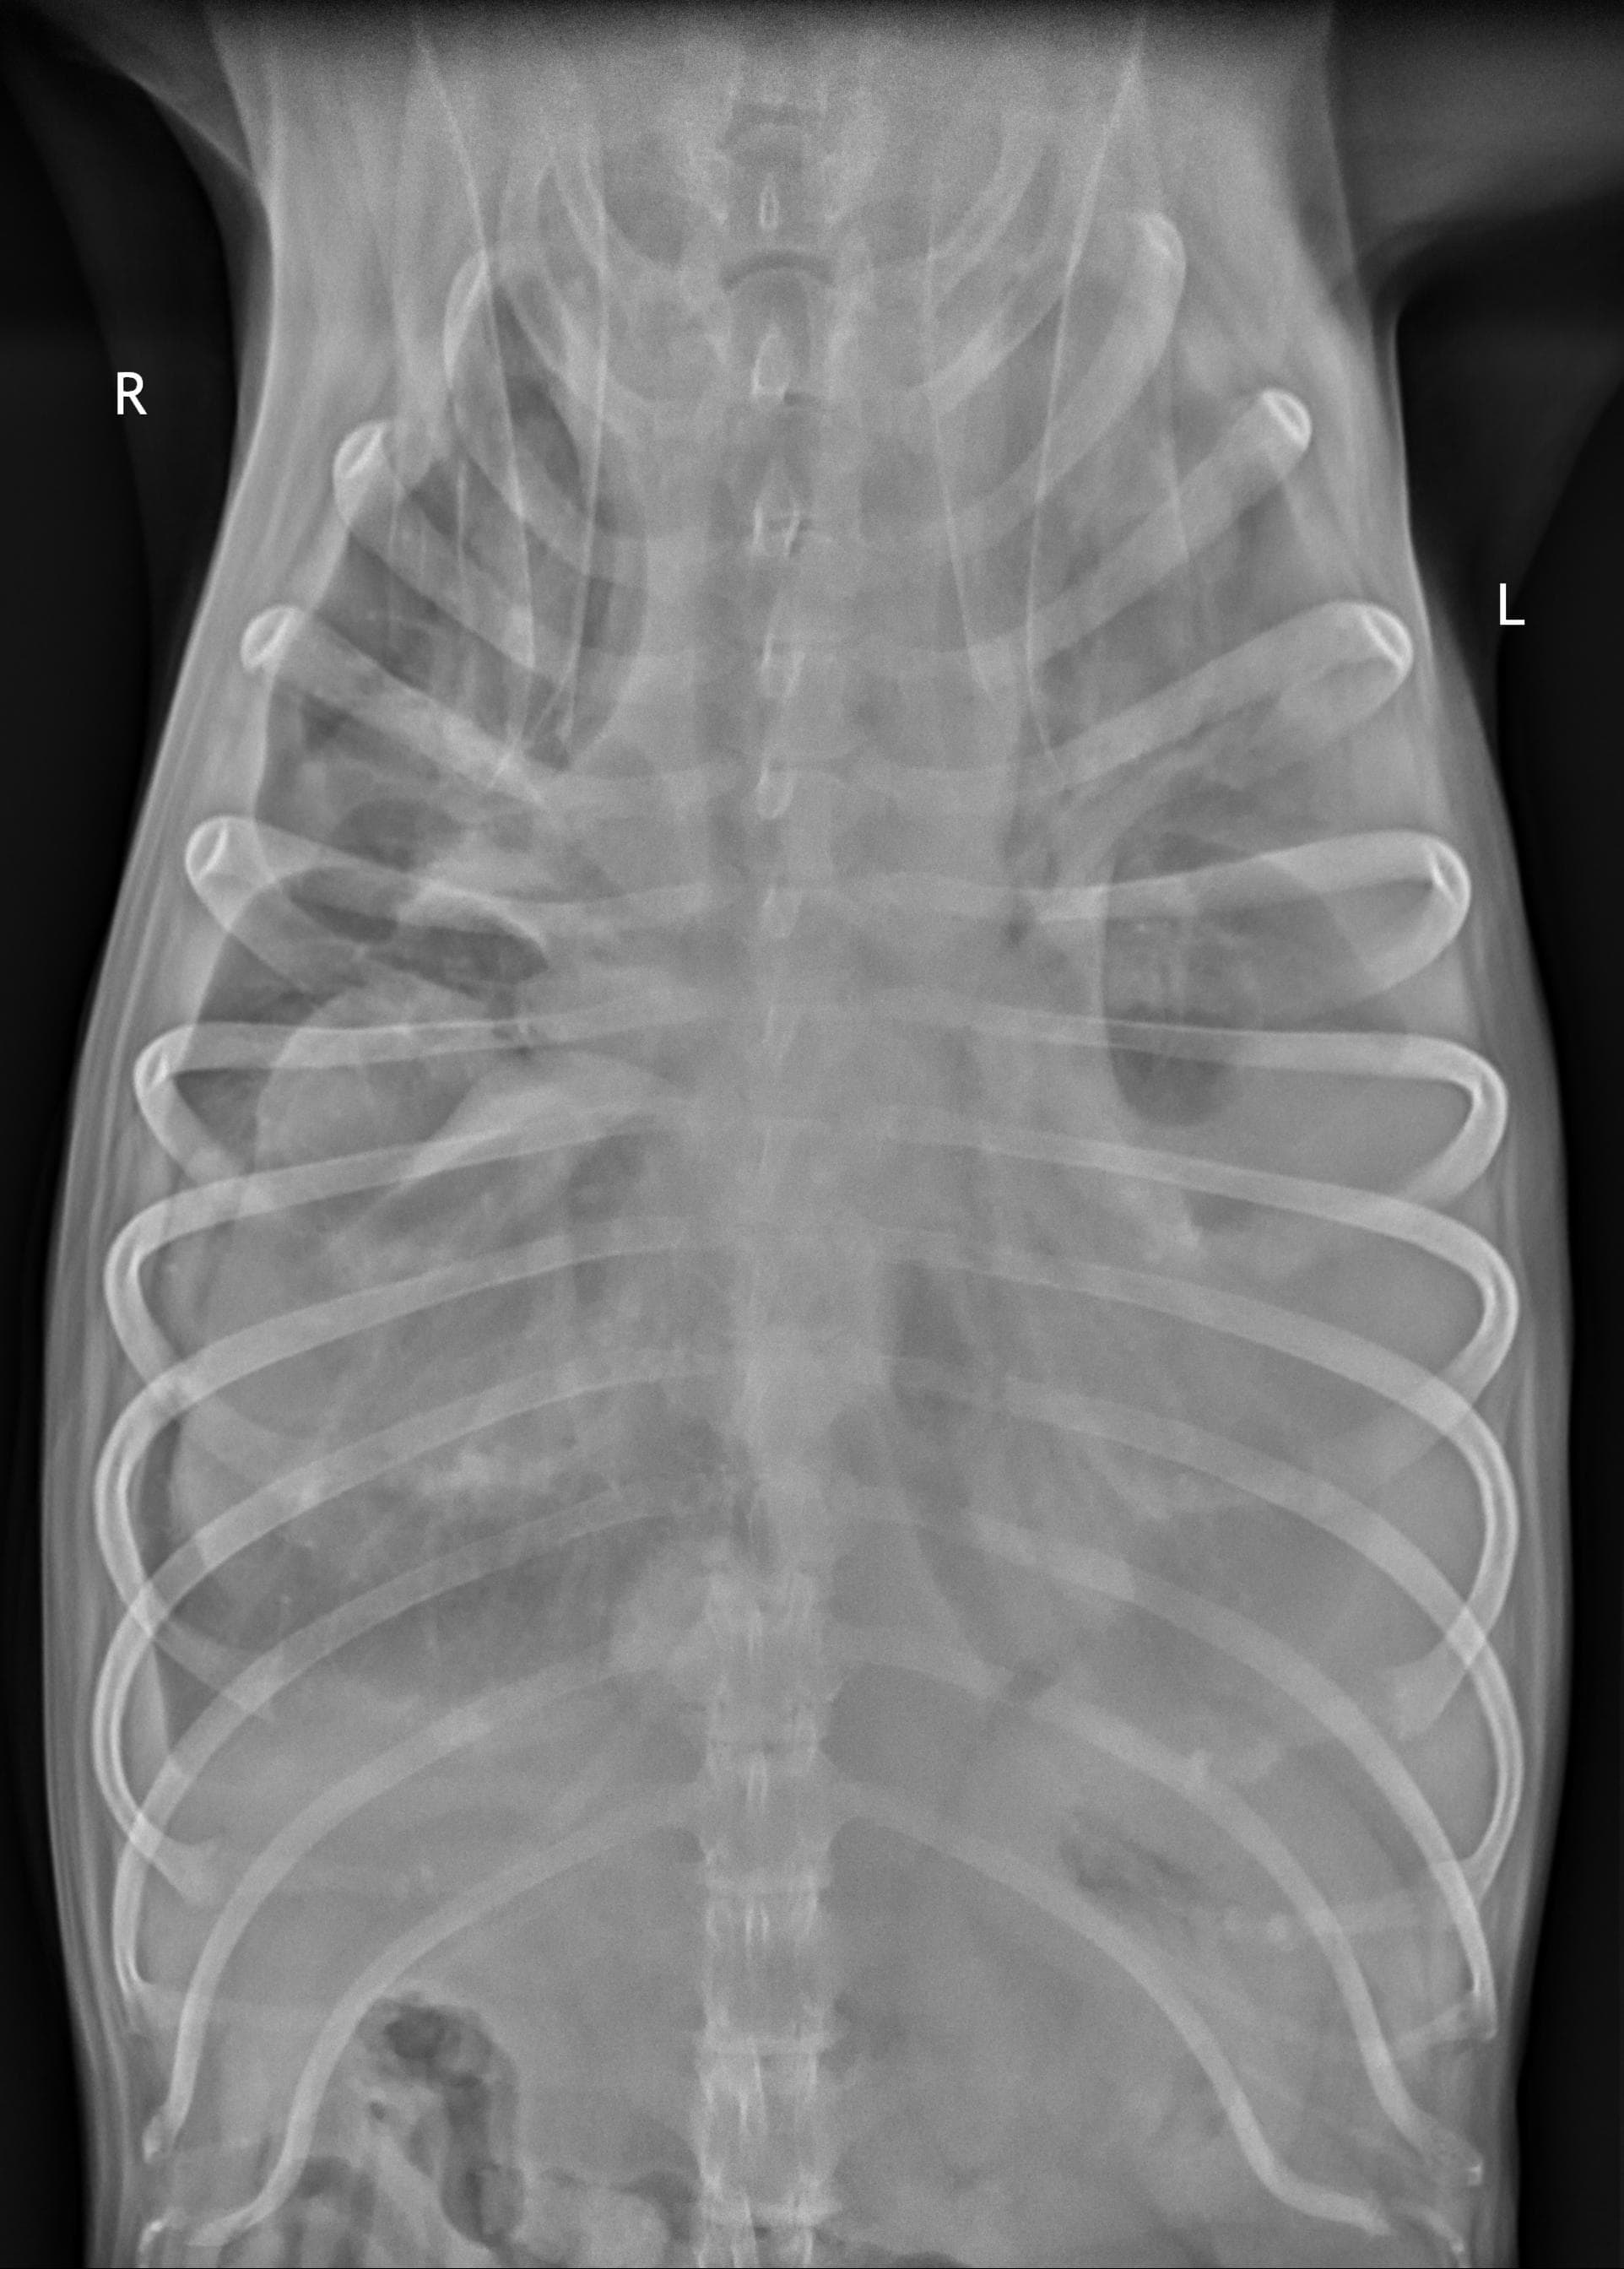

I am in a lot of pain today. My 10yo spayed female dog has had difficulty breathing for about a month or so (getting worse every day) and has lost a lot of weight, although she eats and drinks normally. Vet found severe pleural effusion and drained it (a large dog food bowl worth) and it was bloody, not a good sign. Attached are the x-rays taken today and I would like to know what your opinion is on prognosis and whether it would be wise and humane to pursue this or I should let her go.

Poor Xica! I'm so sorry that she's sick, and that you're in the position of having to consider what is best for her right now. This is always a difficult situation. Her x-rays do appear to show very severe pleural effusion. As I'm sure your veterinarian has probably discussed with you, pleural effusion of the type that you have described (bloody fluid) is almost always caused by one of two things: congestive heart failure, or cancer. The amount of fluid in her chest makes it hard to get a good look at the size and shape of her heart, or to determine if there are any obvious tumors in her chest, so it's hard to say which of these possibilities is more likely without additional testing. But unfortunately, even with aggressive treatment, neither of them have a good long-term prognosis. Knowing this, if I were in your position, I believe I would probably decide to let her go rather than pursuing hospitalization, chest tube placement, etc. - these are invasive, uncomfortable procedures that are unlikely to make a significant difference in the outcome for her, because of the severity of her underlying disease. That being said, the decision of when to consider euthanasia is a very personal choice, and one that is different for every pet owner. If you feel that you need to do everything possible, and want to pursue advanced diagnostics to try and get a more specific answer as to what's wrong, there is nothing wrong with this at all - but if you were my client, I would try to gently caution you that her underlying condition will almost certainly be fatal regardless of what you do. I hope you're able to find peace in your decision, whatever it might be.

These xrays show a number of very concerning findings and the weight loss is a confounding factor. Her prognosis is very poor and if draining the chest has not provided significant relief of her symptoms then yes, euthanasia may be the kind option for Xica. Curative treatment is extremely unlikely and if her respiratory symptoms were not completely resolved with draining then medical management is not expected to maintain adequate comfort either. Remember all the good times she has given you and take comfort in your ability to release her from pain and discomfort at the appropriate time